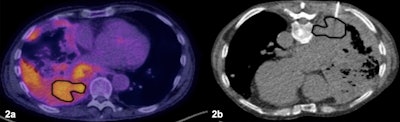

Patient with extensive lung and pleural disease. (2a) The PET/CT was available prior to the biopsy showing heterogeneous F-18 FDG radiotracer uptake and delineating the most accessible area of increased metabolic activity. (2b) The biopsy was targeted to the area of increased activity area and was positive for malignant diagnosis. Image courtesy of the European Journal of Radiology.

In total, 353 CT-guided lung biopsies were performed, with an overall diagnostic rate of 83.9 % (95.8 % malignant). The biopsy success rate was 88.8 % in the PET/CT prebiopsy group versus 78.9% in the group without PET/CT upfront, according to the findings.

Moreover, the biopsy success rate was 88.8 % when the biopsies targeted the PET/CT region showing the maximum tumor metabolic activity region, and only 52.8 % for biopsies that did not target these regions.

“Metabolic information provided by F-18 FDG PET/CT and [percutaneous needle biopsy] localization to the PET/CT maximum activity region is associated with higher diagnostic biopsy rates, especially in masses, and appears to account for improved performance,” the group wrote.